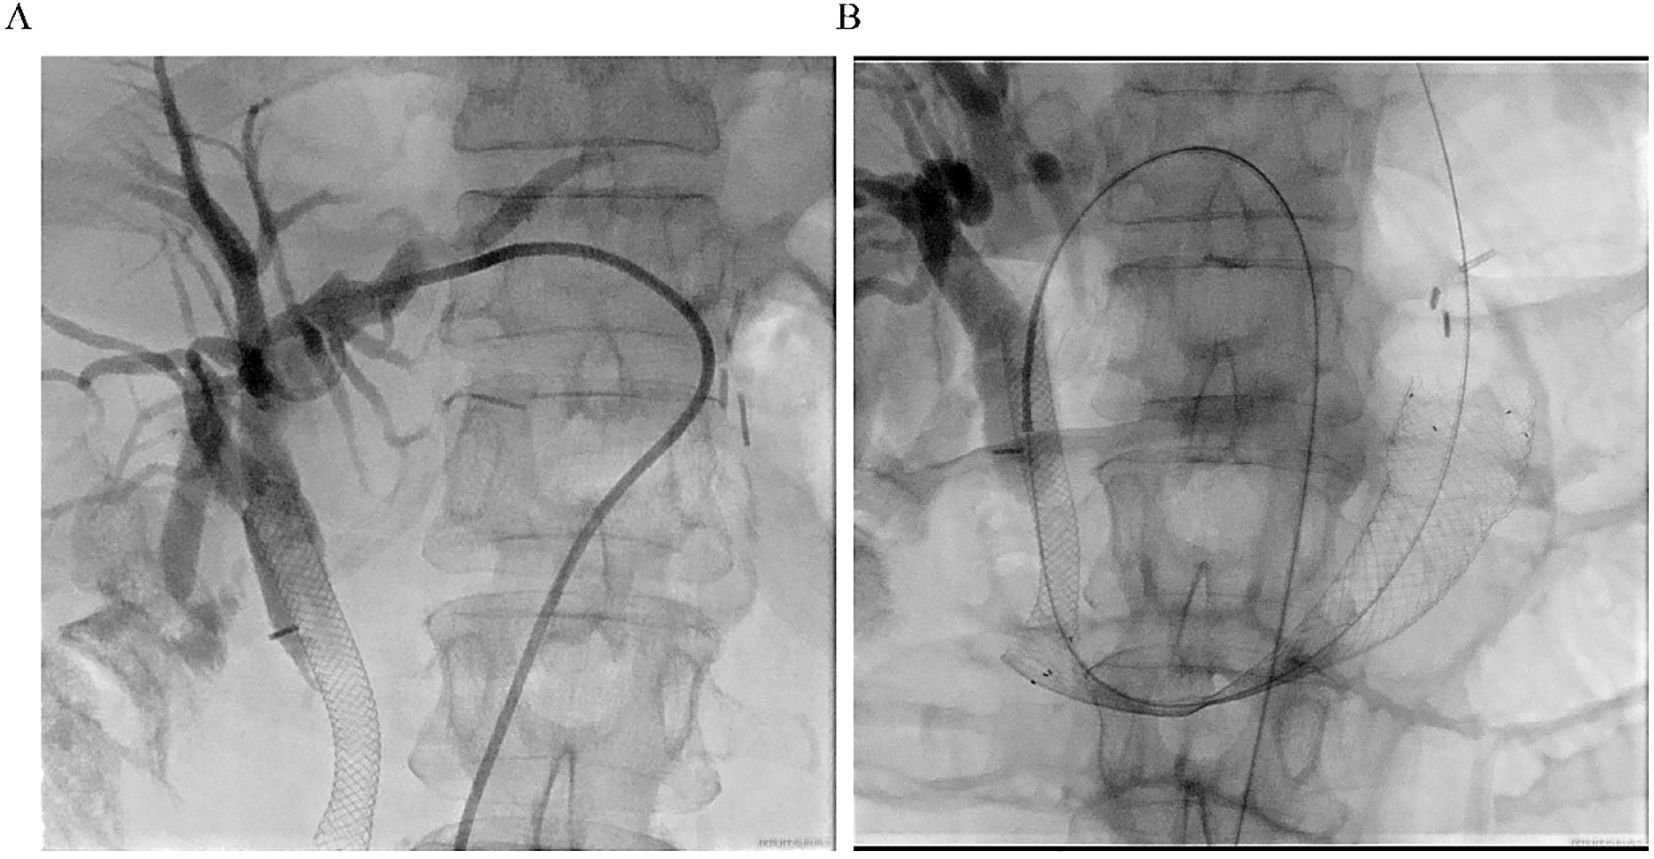

A 63-year-old woman with a prior history of Billroth II gastrectomy for gastric cancer presented in November 2024 with progressive jaundice, persistent nausea, bilious vomiting, and anorexia. Laboratory findings indicated obstructive cholestasis, and PET-CT demonstrated marked thickening of the D2, D3, and D4 portions of the duodenum. The patient was initially diagnosed with obstructive jaundice based on hyperbilirubinemia. Preliminary PET-CT demonstrated duodenal lesions and bile duct obstruction (Figure 1). To alleviate biliary obstruction, percutaneous transhepatic cholangiography and drainage (PTCD) with stent placement were performed. Percutaneous transhepatic cholangiography initially targeted biliary drainage for distal CBD obstruction. Although a percutaneous approach was initially chosen, it only allowed placement of a biliary stent. Dilatation of the percutaneous tract to accommodate the larger duodenal stent (requiring 6–10 Fr) (12) was not feasible, necessitating an endoscopic approach for its placement. Reflux of afferent loop contents into the bile ducts was subsequently observed, prompting placement of a duodenal stent to relieve afferent loop pressure and improve both biliary and bowel obstruction. Subsequent Esophagogastroduodenoscopy (EGD) revealed ALO; However, the ultra-slim endoscope was unable to traverse the narrowed segment, confirming a high-grade stricture.

CT scan images displaying abdominal cross-section and sagittal views. In both images, a red arrow points to a noticeable mass or lesion, while a white arrow marks a significant anatomical structure for reference. The images exhibit varying densities and structures indicative of detailed internal imaging.

Figure 1. Preliminary PET-CT exam. The location of Duodenal lesions (red arrow) and bile duct obstruction (blue arrow) in coronal (A) and transverse (B) positions.